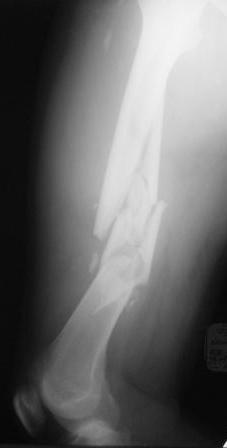

Нужен совет по тактике лечения многооскольчатого перелома бедра |

Хотелось узнать Ваше мнение по тактике лечения многооскольчатого перелома бедра Пациент 26 лет, травма в результате ДТП. Находится на системе скелетного вытяжения. Соматически уже компенсирован. Планируется выполнить остеосинтез бедренной LCP пластиной на тракционном столе, при этом не хотим обнажать зону многооскольчатого перелома. Буду благодарен за критические замечания по предложенной тактике и другие светлые мысли!

Если суставные концы целы (что по приведенному

снимку не очевидно, но будем надеяться, что это так), то сразу подумалось про закрытый интрамедуллярный остеосинтез.

Выбор на пластине основан на том, что проксимальный отломок не цельный, по рентгенограмме видно, что в нём практически до малого вертела имеется осколок. Поэтому у меня опасения, что фиксация внутрикостного стержня в проксимальном отломке не будет достаточно стабильной.

Чем не устраивают реконструкционные и проксимальные гвозди, которые фиксируются вверху за шейку и головку бедра?

В первую очередь мы бы посмотрели более пристально проксимальную часть бедра. Известно, что при переломах диафиза в 20% встречаются ипсилатеральные переломы шейки бедра.

А уже далее последует выбор имплантанта. Если есть ЭОП, то можно поставить гвоздь либо антеградно, либо ретроградно. Если ЭОПа нет, но есть LISS технология, то вполне уместно применить широкую пластину не открывая место перелома.

Эта технология широко известна, обычно обрабатывают обе конечности, что позволяет визуально выполнить коррекцию по длине и ротации. Пластина из малых разрезов без вскрытия зоны перелома позволить сделать стабильную фиксацию (достаточно по 3 уровня фиксации проксимально и дистально).